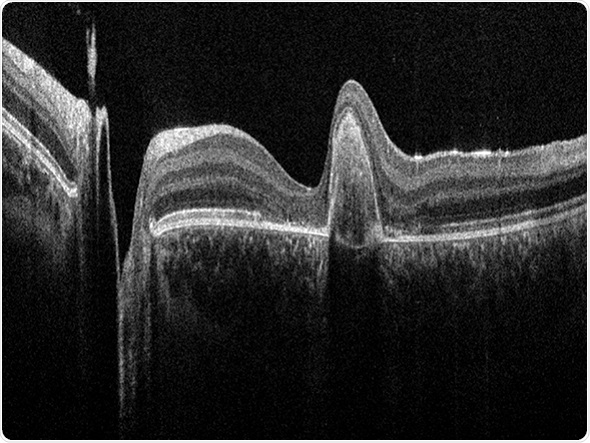

OCT image of human retina acquired with the Bioptigen Envisu C2300

OCT utilizes interferometry to create cross-sectional views of different types of tissue. This non-invasive technique is used to detect and monitor morphological changes of ocular tissue, in particular retinal layer thickness, which can give insight into pathological conditions such as glaucoma, age-related macular degeneration (AMD) or diabetic retinopathy.

Bioptigen develops and manufactures innovative OCT systems and software and is globally successful with products for clinical as well as translational research applications. Using low-power, near-infrared light, Bioptigen OCTs generate high-resolution, volumetric images of the eye. Bioptigen currently markets the FDA-cleared and CE-marked Envisu C2300 OCT for handheld, pediatric, and perioperative applications, and sells advanced ophthalmic OCT imaging systems for preclinical research globally.